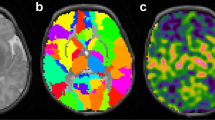

Arterial spin labeling (ASL) magnetic resonance imaging (MRI) can evaluate brain perfusion in neonates noninvasively. The aim of this study was to investigate whether ASL MRI can demonstrate perfusion abnormalities in neonates diagnosed with perinatal arterial ischemic stroke (PAIS).

Pulsed ASL perfusion MR images were acquired in the subacute stage (5–6 d after birth) and at follow-up (13 d to 16 wk after birth) in four PAIS patients. Images were visually evaluated for hypo- and hyperperfusion. In addition, cerebral oxygenation was monitored using near infrared spectroscopy (NIRS).

In three PAIS patients, ASL images showed hypoperfusion in the stroke area. In one of these, hyperperfusion was visualized in the periphery of the stroke area. In one PAIS patient, hyperperfusion was seen in the stroke area. In all infants, cerebral oxygenation was higher in the infarcted hemisphere as compared with the contralateral hemisphere. Follow-up ASL images showed partial recovery of perfusion in the stroke area.

ASL perfusion MRI is able to reliably detect hypo- and hyperperfusion in PAIS patients and can be used to monitor the evolution of perfusion after an ischemic event.